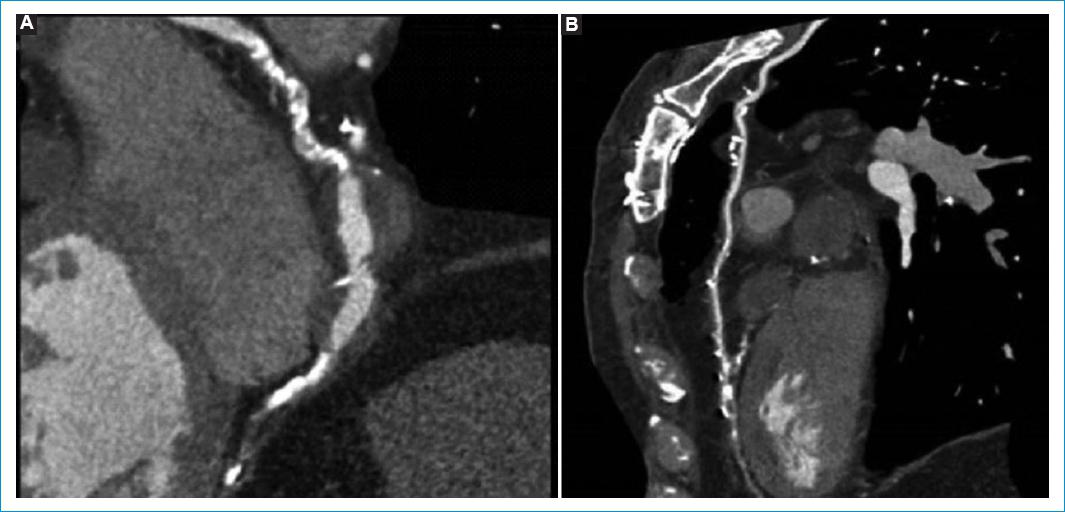

Gracias a la evolución favorable del paciente en los días posteriores a la cirugía, se decidió darle el alta. Posteriormente, se procedió a realizar un seguimiento a los tres meses mediante angiotomografía coronaria, en la que se observaron dilataciones aneurismáticas graves en el tercio medio de la arteria descendente anterior. Además, se visualizó un puente arterial mamario a la descendente anterior que se encontraba permeable. En lo que respecta a la coronaria derecha, se observó gran dilatación en su tercio medio (Fig. 2). La razón de llevar a cabo el seguimiento mediante angiotomografía se debió a la necesidad de verificar el estado de permeabilidad de los puentes coronarios. Para tal fin, se optó por realizar una tomografía, dado que se trata de un procedimiento no invasivo y es menos costoso en comparación con la angiografía.

Figura 2 Angiotomografía coronaria de seguimiento realizada luego de tres meses. A: se aprecia dilatación aguda de la coronaria derecha en su tercio medio. B: se observan dilataciones aneurismáticas graves en el tercio medio de la arteria descendente anterior y puente arterial mamario a la descendente anterior permeable.